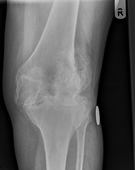

X-ray of knee, showing severe osteoarthritis of the joint, with bone loss, and subluxation of the joint.